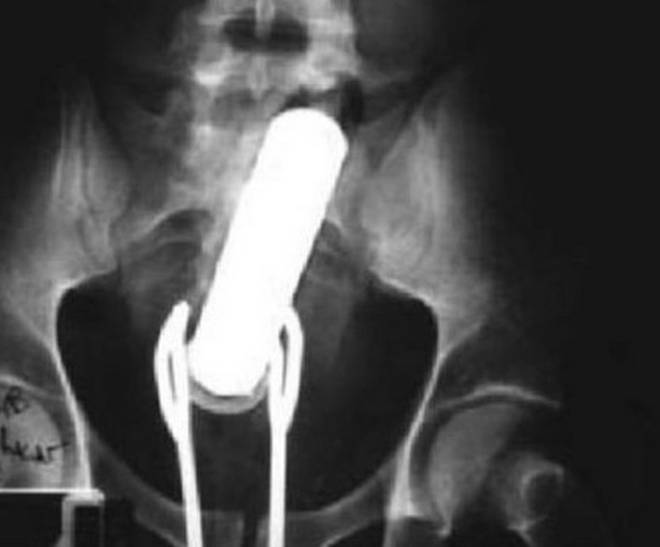

Tutte queste persone sono state ricoverate con diversi oggetti incastrati nell’ano e non solo: dal cellulare alle chiavi di casa, passando per proiettili e giocattoli come macchinine e pupazzetti.

Anche il sex toy, a quanto pare deve essere usato responsabilmente. Specialmente quando l’oggetto è improvvisato. E chi rimane con l’oggetto incastrato cosa deve fare? Come spiegano i medici dei pronto soccorso, non bisogna provare a risolvere il problema da soli senza andare in ospedale. In molti casi infatti, alcune persone vengono ricoverate sia con l’oggetto, sia con le pinze utilizzate per recuperare l’oggetto, conficcate nell’ano.